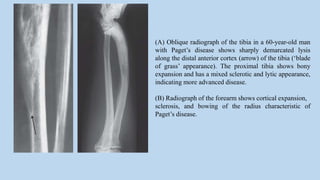

(A) Oblique radiograph of the tibia in a 60-year-old man

with Paget’s disease shows sharply demarcated lysis

along the distal anterior cortex (arrow) of the tibia (‘blade

of grass’ appearance). The proximal tibia shows bony

expansion and has a mixed sclerotic and lytic appearance,

indicating more advanced disease.

(B) Radiograph of the forearm shows cortical expansion,

sclerosis, and bowing of the radius characteristic of

Paget’s disease.